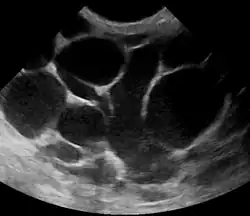

An ultrasound image of puerperal mastitis

Puerperal mastitis is the inflammation of the breast in connection with pregnancy, breastfeeding or weaning. Since one of the most prominent symptoms is tension and engorgement of the breast, it is thought to be caused by blocked milk ducts or milk excess. It is relatively common; estimates range depending on methodology between 5–33%. However, only about 0.4–0.5% of breastfeeding mothers develop an abscess.[8]

Risk factors include poor latch, cracked nipples, and weaning.[1] Use of a breast pump has historically been associated with mastitis, but has been determined as an indirect association.[7] The bacteria most commonly involved are Staphylococcus and Streptococci.[1] Diagnosis is typically based on symptoms.[2] Ultrasound may be useful for detecting a potential abscess.[1]

The diagnosis of mastitis and breast abscess can usually be made based on a physical examination.[24] The doctor will also take into account the signs and symptoms of the condition.

However, if the doctor is not sure whether the mass is an abscess or a tumor, a breast ultrasound may be performed. The ultrasound provides a clear image of the breast tissue and may be helpful in distinguishing between simple mastitis and abscess or in diagnosing an abscess deep in the breast. The test consists of placing an ultrasound probe over the breast.